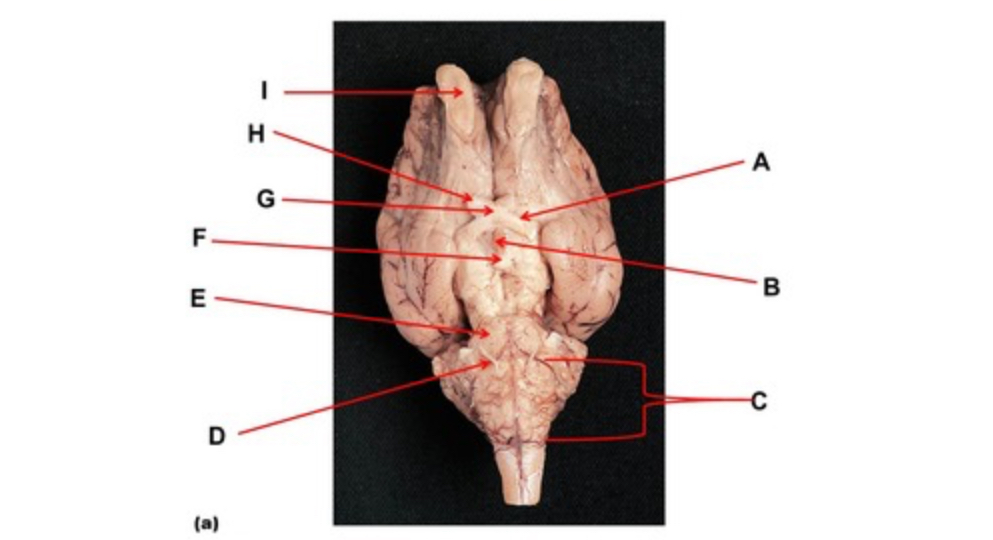

Name the region within bracket D.

medulla

Name the region within bracket D

medulla

Name the deep groove at the tip of arrow G.

anterior median fissure